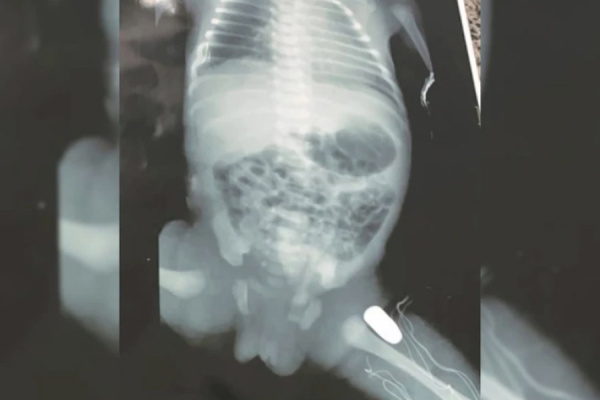

Avião vindo da Venezuela desobedeceu ordens para pousar e foi abatido; drogas transportadas pelos suspeitos foram apreendidas.